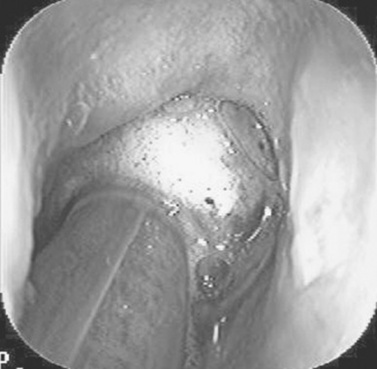

Endoscopy of the rectum and distal small colon can be performed with most flexible endoscopes in use in equine practice and should be preceded, as much as possible, by evacuation and saline lavage of the rectum and distal small colon. The mucosal surface should appear pink to pale red and should have a smooth, “velvety” appearance. Mucosal edema or thickening, hyperemia, irregularities, defects, tears, and intraluminal masses are abnormal findings. Because of the concern for trauma to the rectum and small colon, the horse should be adequately sedated and restrained before preparation and examination of the distal alimentary tract.